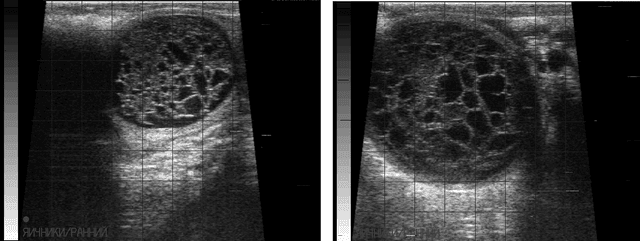

А что если я скажу, что в последнее время мировое сообщество определило кисты 3го типа? А 95% тел, которые мы диагностируем как лютеиновые кисты, не являются таковыми и в целом не требуют затрат на их лечение и каких-либо манипуляций?

Возвращаясь к Вашему комментарию, соглашусь по поводу 3го случая, он очень спорный и разные специалисты будут его трактовать по разному.

И касательно этого снимка, я согласен что также (как трабекулы) могут светиться лизированные эритроциты, полость обычно схлопывается и заростает через 20-30 дней, (около 90%).